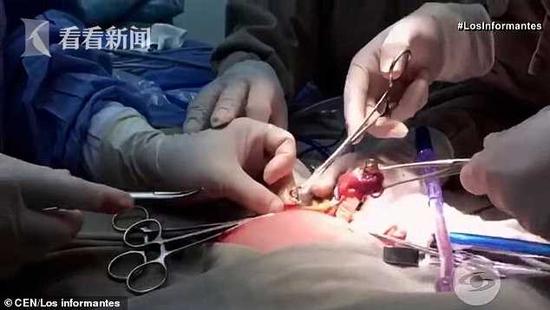

据英国《每日邮报》3月20日报道,哥伦比亚的巴兰基亚市最近降生了一个罕见的“胎中胎”双胞胎,姐姐腹中长着妹妹,妹妹仅发育了四肢,为保证姐姐的存活,医生不得不手术取出妹妹。

这名“胎中胎”双胞胎姐姐名叫伊扎马拉,上月22日在妈妈子肚子里待了37周的时候剖腹产来到世上,当时的体重为6.3斤,同正常婴儿差不多。

伊扎马拉之所以接受剖腹产,是因为在35周大的时候,妈妈的产科医生通过3D/4D超声技术,发现伊扎马拉的腹中似乎有一个囊肿。经过仔细观察后,医生发现这个囊肿是一个胎儿,有四肢但没有心脏和大脑,且还在不断长大。

医生确诊这是一例典型的“胎中胎”双胞胎。为了保证正常胎儿的发育,阻止“胎中胎”胎儿的生长损坏正常胎儿的内脏器官,医生不得不提早做了剖腹产手术。

伊扎马拉降生后,医生很快也为她做了手术,将其腹中未成形的45毫米长14克重的妹妹取出。如今,伊扎马拉即将满月,健康发育状况良好,同正常同龄孩子一样。

专家说,最早有文字记载的“胎中胎”双胞胎案例出现在1808年,它是因为双胞胎细胞没有完全分离导致的,其中一个通过胎盘与母亲相连,另一个较小的通过胎盘与其双胞胎的血管相连。随着大双胞胎的成长,小双胞胎会被吸收到腹部。这种病例大部分发生在亚洲国家和地区,而且常常是在胎儿降生后才被发现。